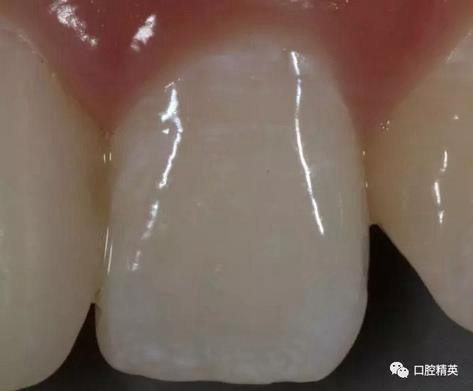

比色,記錄鄰牙顏色細(xì)節(jié)

修復(fù)體展示

口內(nèi)正側(cè)位及切端特寫